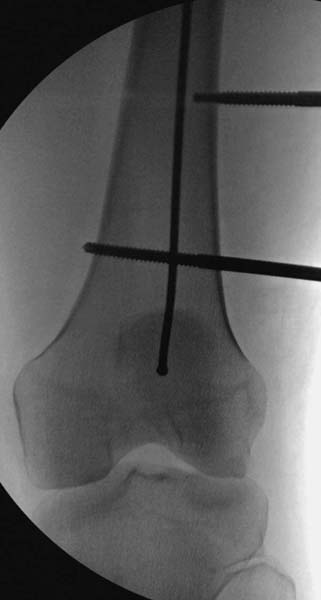

Остеосинтез бедра не стали делать из-за множественных переломов ребер с ушибом грудной клетки и поэтом у закончили фиксацию бедра наружным фиксатором.

Около 11.00 вечера больная переведена в реанимацию, без сознания, но стабильная.. На третьий день провели стабилизацию перелома бедра антеградным остеосинтезом.

Закрытый БИОС решает множественные проблемы связанные с лечением переломов, но проблема дистальной блокировки без рентгена до сих пор остается нерешенной. Рекламированные производителями приспособления для дистальной блокировки из-за различной кривизны кости не эффективны или стоит очень дорого (Smith&Nephew SureLock). Задержка операции из-за блокировки не всегда удовлетворяет, и многих вынуждает искать альтернативные методы фиксации. С результатами таких действий, остеомиелитом и несращениями, встречаемся в ежедневной жизни..

Для решения проблемы дистальной блокировки компания DigiMed недавно предложила систему блокировки без рентгена. Пока в стране только два набора и только для антеградных гвоздей, но компания работает над созданием устроиства для других гвоздей тоже..

Результат первых случаев показала отсутствие разницы между занятиями на муляжах, а также Workshop и с удивительной точностью вывел латерально над кожей специальное сверло. Дальше по сверлу тонкий направитель и проводится сверление каннюлированным сверлом....